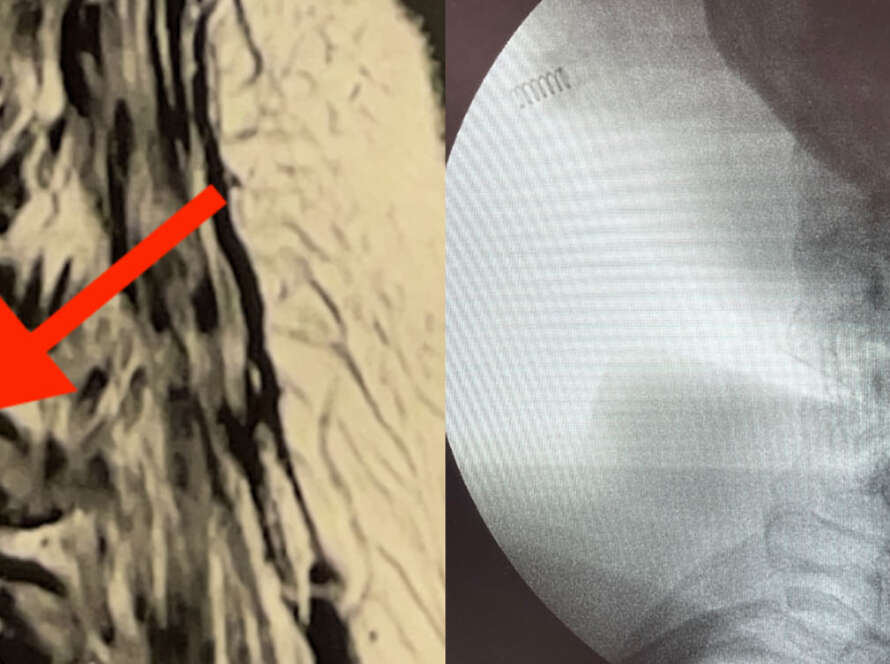

Exemplo de compressão neurológica causada por hérnia de disco extrusa.

Ressonância nuclear magnética evidenciando hérnia discal L5-S1 à esquerda com compressão dos nervos.